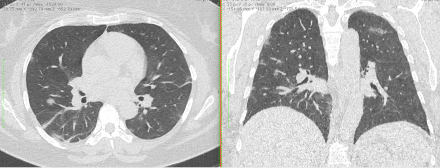

2. Наличие клинических проявлений, указанных в п. 1, в сочетании с характерными изменениями в легких по данным компьютерной томографии (КТ) (см. Приложение 1 настоящих рекомендаций) вне зависимости от результатов однократного лабораторного исследования на наличие РНК SARS-CoV-2 и эпидемиологического анамнеза.

- Изменения при КТ (рентгенографии), типичные для вирусного поражения (объем поражения минимальный или средний; КТ 1 - 2)

- Изменения в легких при КТ (рентгенографии), типичные для вирусного поражения (объем поражения значительный или субтотальный; КТ 3 - 4)

- Изменения в легких при КТ (рентгенографии), типичные для вирусного поражения критической степени (объем поражения значительный или субтотальный; КТ 4) или картина ОРДС.

Методы лучевой диагностики применяют для выявления COVID-19 пневмоний, их осложнений, дифференциальной диагностики с другими заболеваниями легких, а также для определения степени выраженности и динамики изменений, оценки эффективности проводимой терапии.

КТ имеет высокую чувствительность в выявлении изменений в легких, характерных для COVID-19. Применение КТ целесообразно для первичной оценки состояния ОГК у пациентов с тяжелыми прогрессирующими формами заболевания, а также для дифференциальной диагностики выявленных изменений и оценки динамики процесса. КТ позволяет выявить характерные изменения в легких у пациентов с COVID-19 еще до появления положительных лабораторных тестов на инфекцию с помощью МАНК. В то же время, КТ выявляет изменения легких у значительного числа пациентов с бессимптомной и легкой формами заболевания, которым не требуется госпитализация. Результаты КТ в этих случаях не влияют на тактику лечения и прогноз заболевания при наличии лабораторного подтверждения COVID-19. Поэтому массовое применение КТ для скрининга асимптомных и легких форм болезни не рекомендуется.

4. Все выявляемые при лучевых исследованиях признаки, включая КТ-симптомы, не являются специфичными для какого-либо вида инфекции и не позволяют установить этиологический диагноз. Вне клинической (эпидемической) ситуации они не позволяют отнести выявленные изменения к пневмонии COVID-19 и дифференцировать их с другими пневмониями и невоспалительными заболеваниями. Данные лучевого исследования не заменяют результаты обследования на РНК SARS-CoV-2. Отсутствие изменений при КТ не исключают наличие COVID-19 и возможность развития пневмонии после проведения исследования.